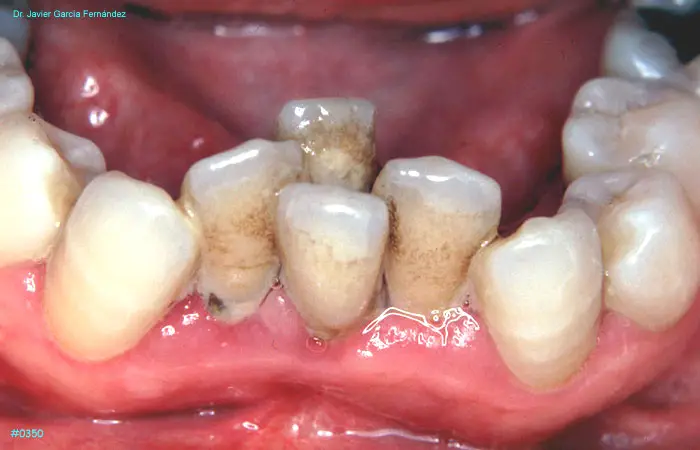

ATLAS DE CIRUGIA PERIODONTAL